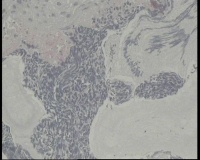

镜下见鳞状上皮大部分如(图1) ,仅局灶鳞状上皮异型(图2-4),细胞似牵拉变形,部分腺腔内见异型细胞团,这些细胞跟LEEP刀手术电凝有关系吗?这个怎么报?累腺明显,上皮图1怎么报?能报CINII—III累及腺体吗?还是宫颈高级别鳞状上皮内病变累及腺体

图2

CIN2-3累腺,有机械损伤,要按1-12点分别报告,要报告内外切缘情况。